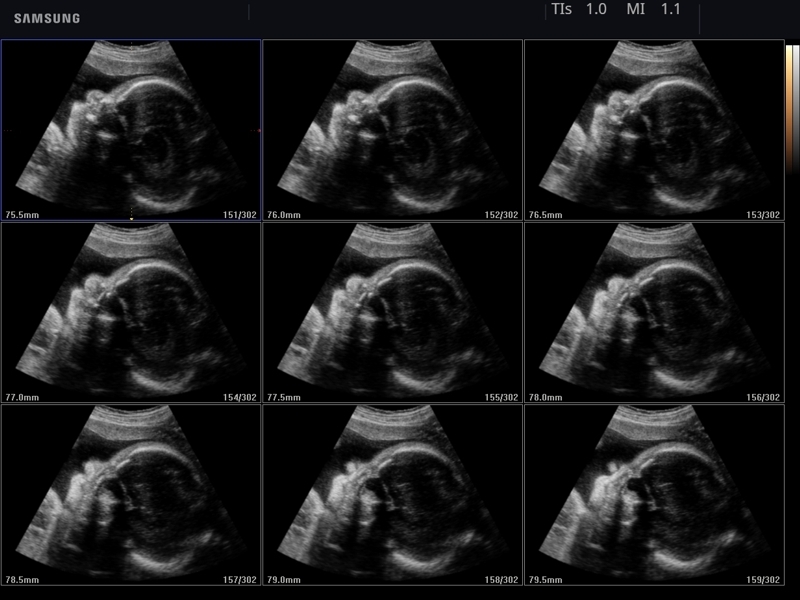

• Модуль 5D Heart Color - позволяет исследовать структуры сердца плода на предмет потенциальных нарушений кровотока, что является важной составляющей эхокардиографического исследования плода. Используя объемные данные STIC и ЦДК, строятся 9 стандартных эхокардиографических срезов плода на одном экране.

• MSV (Multi-Slice View или мультислайсинг) - возможность одновременного просмотра на экране множественных срезов, полученных при трехмерном сканировании.

• VolumeCT - трехмерная реконструкция изображений в виде куба (Cube Sectional View) или трех пересекающихся плоскостей (Cross View).